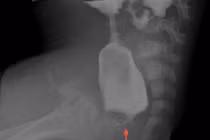

Can thiệp rò hậu môn dưới sự hướng dẫn của siêu âm - Ảnh BVCC

Diễn biến trong mổ: Ê-kíp Ngoại khoa phối hợp chặt chẽ với Gây mê hồi sức để đảm bảo thao tác chính xác, giảm sang chấn cho người bệnh. Khi siêu âm làm rõ bản đồ đường rò, phẫu thuật viên tiến hành xử trí triệt để từng nhánh rò, giữ tối đa cấu trúc cơ thắt.